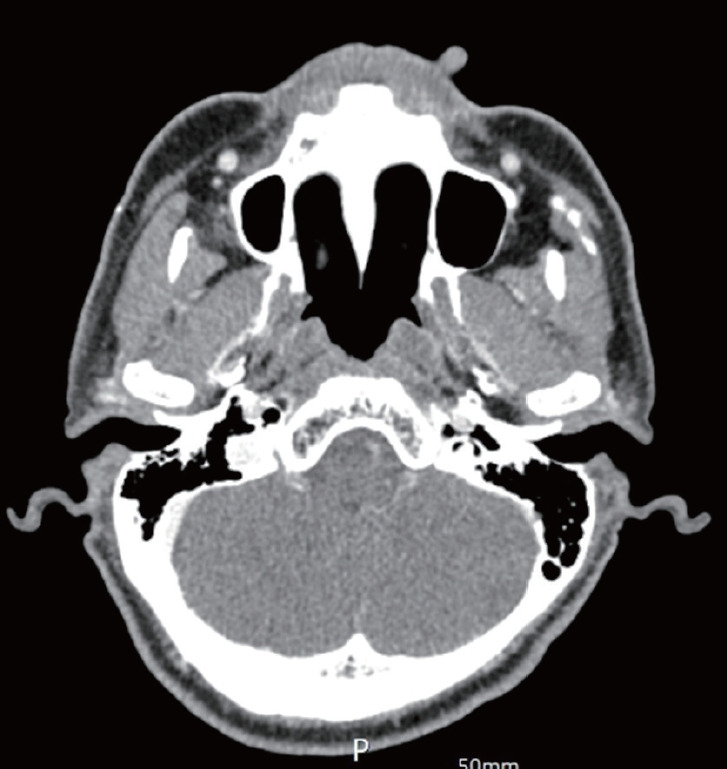

多形性腺瘤是一种可发生在唾液腺的良性肿瘤,最常见于腮腺。虽然它主要发生在大唾液腺中,但有时也会在小唾液腺中发现。在小唾液腺中,它最常起源于硬腭和软腭,较少见于上唇。由于位于小唾液腺,大多数多形性腺瘤会累及粘膜并突出粘膜。一名 61 岁的男性上唇皮肤上长有 1.5 厘米的外生肿块。肿块位于皮肤外,没有累及或突出到唇内粘膜。肿块被完全切除,随后的永久性活检诊断为多形性腺瘤。在这种情况下,体格检查时怀疑多形性腺瘤很有难度,可能会导致诊断混乱。它还可能被误认为是包涵囊肿或其他类型的肿块,因此很容易在未核实病理结果的情况下进行治疗。

Pleomorphic adenoma is a benign tumor that can occur in the salivary glands, most commonly in the parotid gland. While it primarily occurs in the major salivary glands, it can sometimes be found in the minor salivary glands. Within the minor salivary glands, it most often originates in the hard palate and soft palate, and less frequently in the upper lips. Due to its location in the minor salivary glands, most pleomorphic adenoma involve and protrude on the mucosa. A 61-year-old man presented with 1.5 cm exophytic mass on the skin of his upper lip. This mass was exophytic on the skin and did not involve or protrude into the inner lip mucosa. The mass was entirely excised, and a subsequent permanent biopsy diagnosed it as a pleomorphic adenoma. In such situations, it can be challenging to suspect pleomorphic adenoma during a physical examination, leading to potential diagnostic confusion. It might also be mistaken for an inclusion cyst or another type of mass, making it tempting to treat without verifying the pathological results.